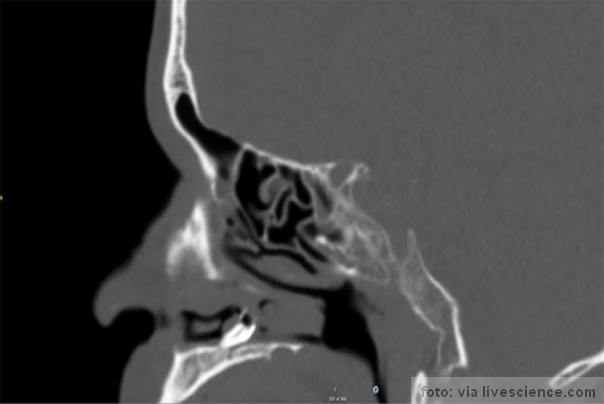

zub u nosu CT snimak FOTO:BMJ Case Reports

Na kraju on je posetio univerzitetsku bolnicu u mestu Aarhus gde su mu nakon pregleda lekara otkrili masu pokrivenu sluzom na dnu nosne šupljine.

Doktori su hitno reagovali, jer su sumnjali da ima cistu. Operisan je i lekari su na kraju dokorri su ostali šokirani jer su mu izvadili pravi zubkoji je bio pokriven upaljenim tkivom nosa.

Nisu otkrili razloge zbog kojih se zub nalazio u nosu, ali su naveli da su ovakvi slučajevi medicinski ekstremno retki javljaju se u samo 0,1 do 1 posto populacije i uglavnom su zableženi kod muškaraca

Pacijent je u mladosti doživeo traumu lica (slomljena mu je čeljust i nos), doktori su izjavili da ova ozljeda verojatno nije uzrok rasta zuba u nosu,jendostavno to je medicinski retki fenomen.!